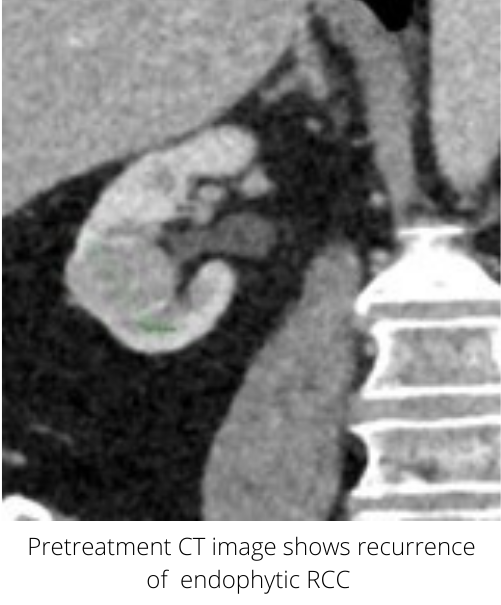

Recurrence of renal cell carcinoma treated with microwave ablation Laser Ablation Renal Cell Carcinoma Learn how interventional radiology uses imaging and minimally invasive procedures to treat kidney tumors with ablation. Learn about renal cell carcinoma (rcc), the most common type of kidney cancer, and its causes, risk factors, diagnosis and treatment. Learn about the different types of ablation, how they are. 1 of these new cases, 85% will be. Ablation can be performed percutaneously. Laser Ablation Renal Cell Carcinoma.